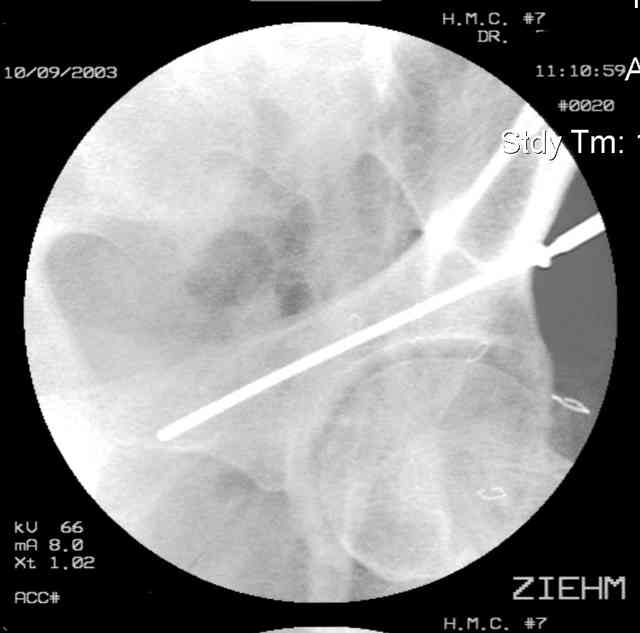

Here's a pic from the foot of the bed and you can see the clamp in the wound and the knee is extended so he must've had a tight rectus. The C-arm is rolled back to an obturator oblique image to reveal the anterior column...we put a slight outlet tilt to combine the images and give a better view of the anterior column...we can see the posterior column limb reduction in the wound, we can palpate the quadrilateral surface limb, and the image demonstrates the anterior column portion...you can adjust the tilt and rotation to image tangentially to the fracture plane if you'd like. We've inserted a 2mm K wire to site the starting point and aim/orientation for the drill and screw

Prone Imaging

same image, just another look.